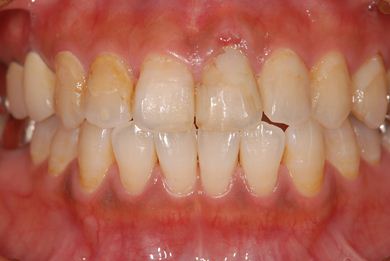

抜歯即日スピードインプラント治療

| 性別/年齢 | 女性 / 39歳 | ||||||||||||||||||||||||||||||||

| 主訴 | 左前歯の虫歯治療を希望。 | ||||||||||||||||||||||||||||||||

| 治療内容 | インプラント1本(抜歯即日スピードインプラント)、メタルボンドセラミック1本 | ||||||||||||||||||||||||||||||||

| 総治療費 | 458,588円 | ||||||||||||||||||||||||||||||||

| 治療期間 | 1年0ヶ月 |